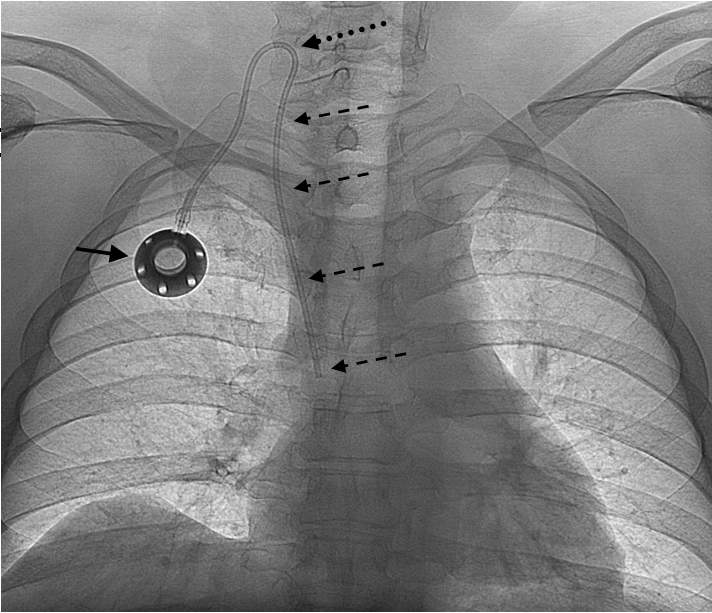

Placement of chronic venous lines and ports in Hungary are usually done by anethesiologists, whereas in many countries in Europe and in a few centers in Hungary it is performed by interventional radiologists; image-guidance (US-guided puncture, fluoroscopy guided placement of the catheter tip) reduces the risk of complications. Chronic venous access is necessary when chemotherapy, antibiotic therapy or total parenteral nutrition is needed for a number of weeks or months. The advantage of port is that it is placed into a subcutaneous pouch (as opposed to the Hickman line, which has a large portion of the catheters outside the skin) thus the quality of life of the patient is much better. The port is (almost) invisible, regular lifestyle including showers and swimming is possible, it can be used for many months or even 1-2 years, and it can be punctuted more than 1000 times; the catheter is tunneled from this pouch to the internal jugular vein or the subclavian vein; the tip of this catheter is in the distal portion of the superior vena cava (Figure 10). Most important immediate complications at these procedures include PTX, inadvertent arterial puncture, venous wall perforation, air-embolism, catheter malposition; delayed complications include infection, venous stenosis, formation of thrombus or fibrin sheath.

Figure 10. Port implantation. The port chamber is indicated by the solid arrow. The plastic catheter from the port chamber is directed through a subcutaneous tunnel into the internal jugular vein and the superior vena cava (dashed arrows). Internal jugular vein was punctured using ultrasound guidance.